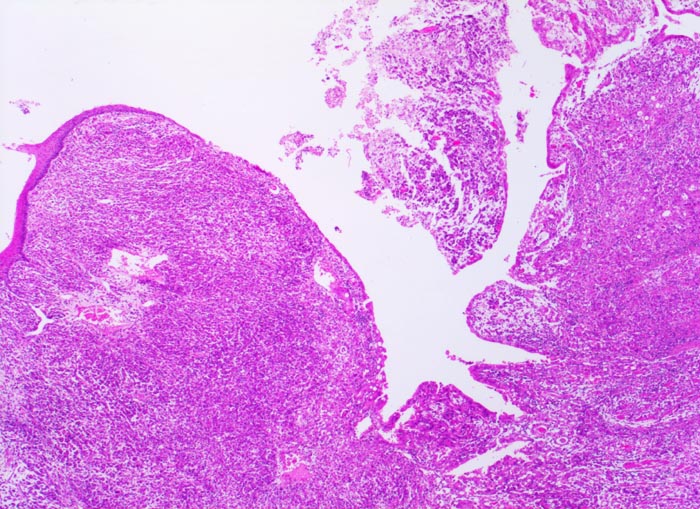

• Gewebsfragment aus gastroösophagealem Übergang.

• Das unscharf begrenzte Karzinom breitet sich diffus in der gesamten Magenwand und in der Ösophaguswand aus bis in des periösophageale und subseröse Fettgewebe.

• Ösophagus mit intaktem plattenepithelialem Schleimhautüberzug.